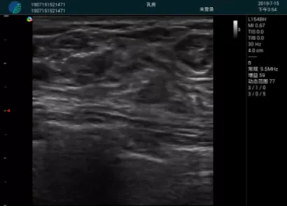

清晰顯示腺體內(nèi)低回聲快影,邊界清晰,包膜較光滑

確定進(jìn)針路徑并實(shí)時(shí)監(jiān)測(cè)抽吸針與腫塊位置關(guān)系